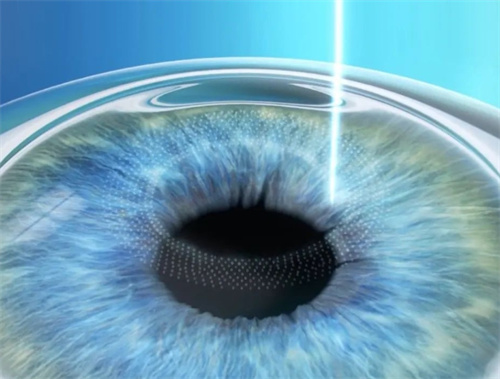

3. 飞秒辅助ICL(智臻飞秒ICL)

飞秒ICL(基础版):3.36万~3.7万元/双眼(郑州爱尔眼科3.36万元起)

飞秒TICL(散光版):3.76万~4.1万元/双眼(郑州爱尔眼科3.76万元起)

适用人群:

追求更高精密度的患者

近视超1800度且散光显著者

手术方式:飞秒辅助ICL比传统ICL贵6000~8000元。